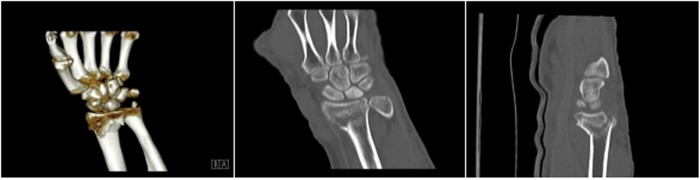

明峰CT搭載了領先的硬件技術平臺及系統,強大的掃描能力可滿足臨床的各種要求,呈現更極致的細節,為各臨床科室提供高品質的圖像。薄層掃描,消除部分容積效應,提高各向同性。配合高分辨率算法,有助于細微結構和形態學顯示。